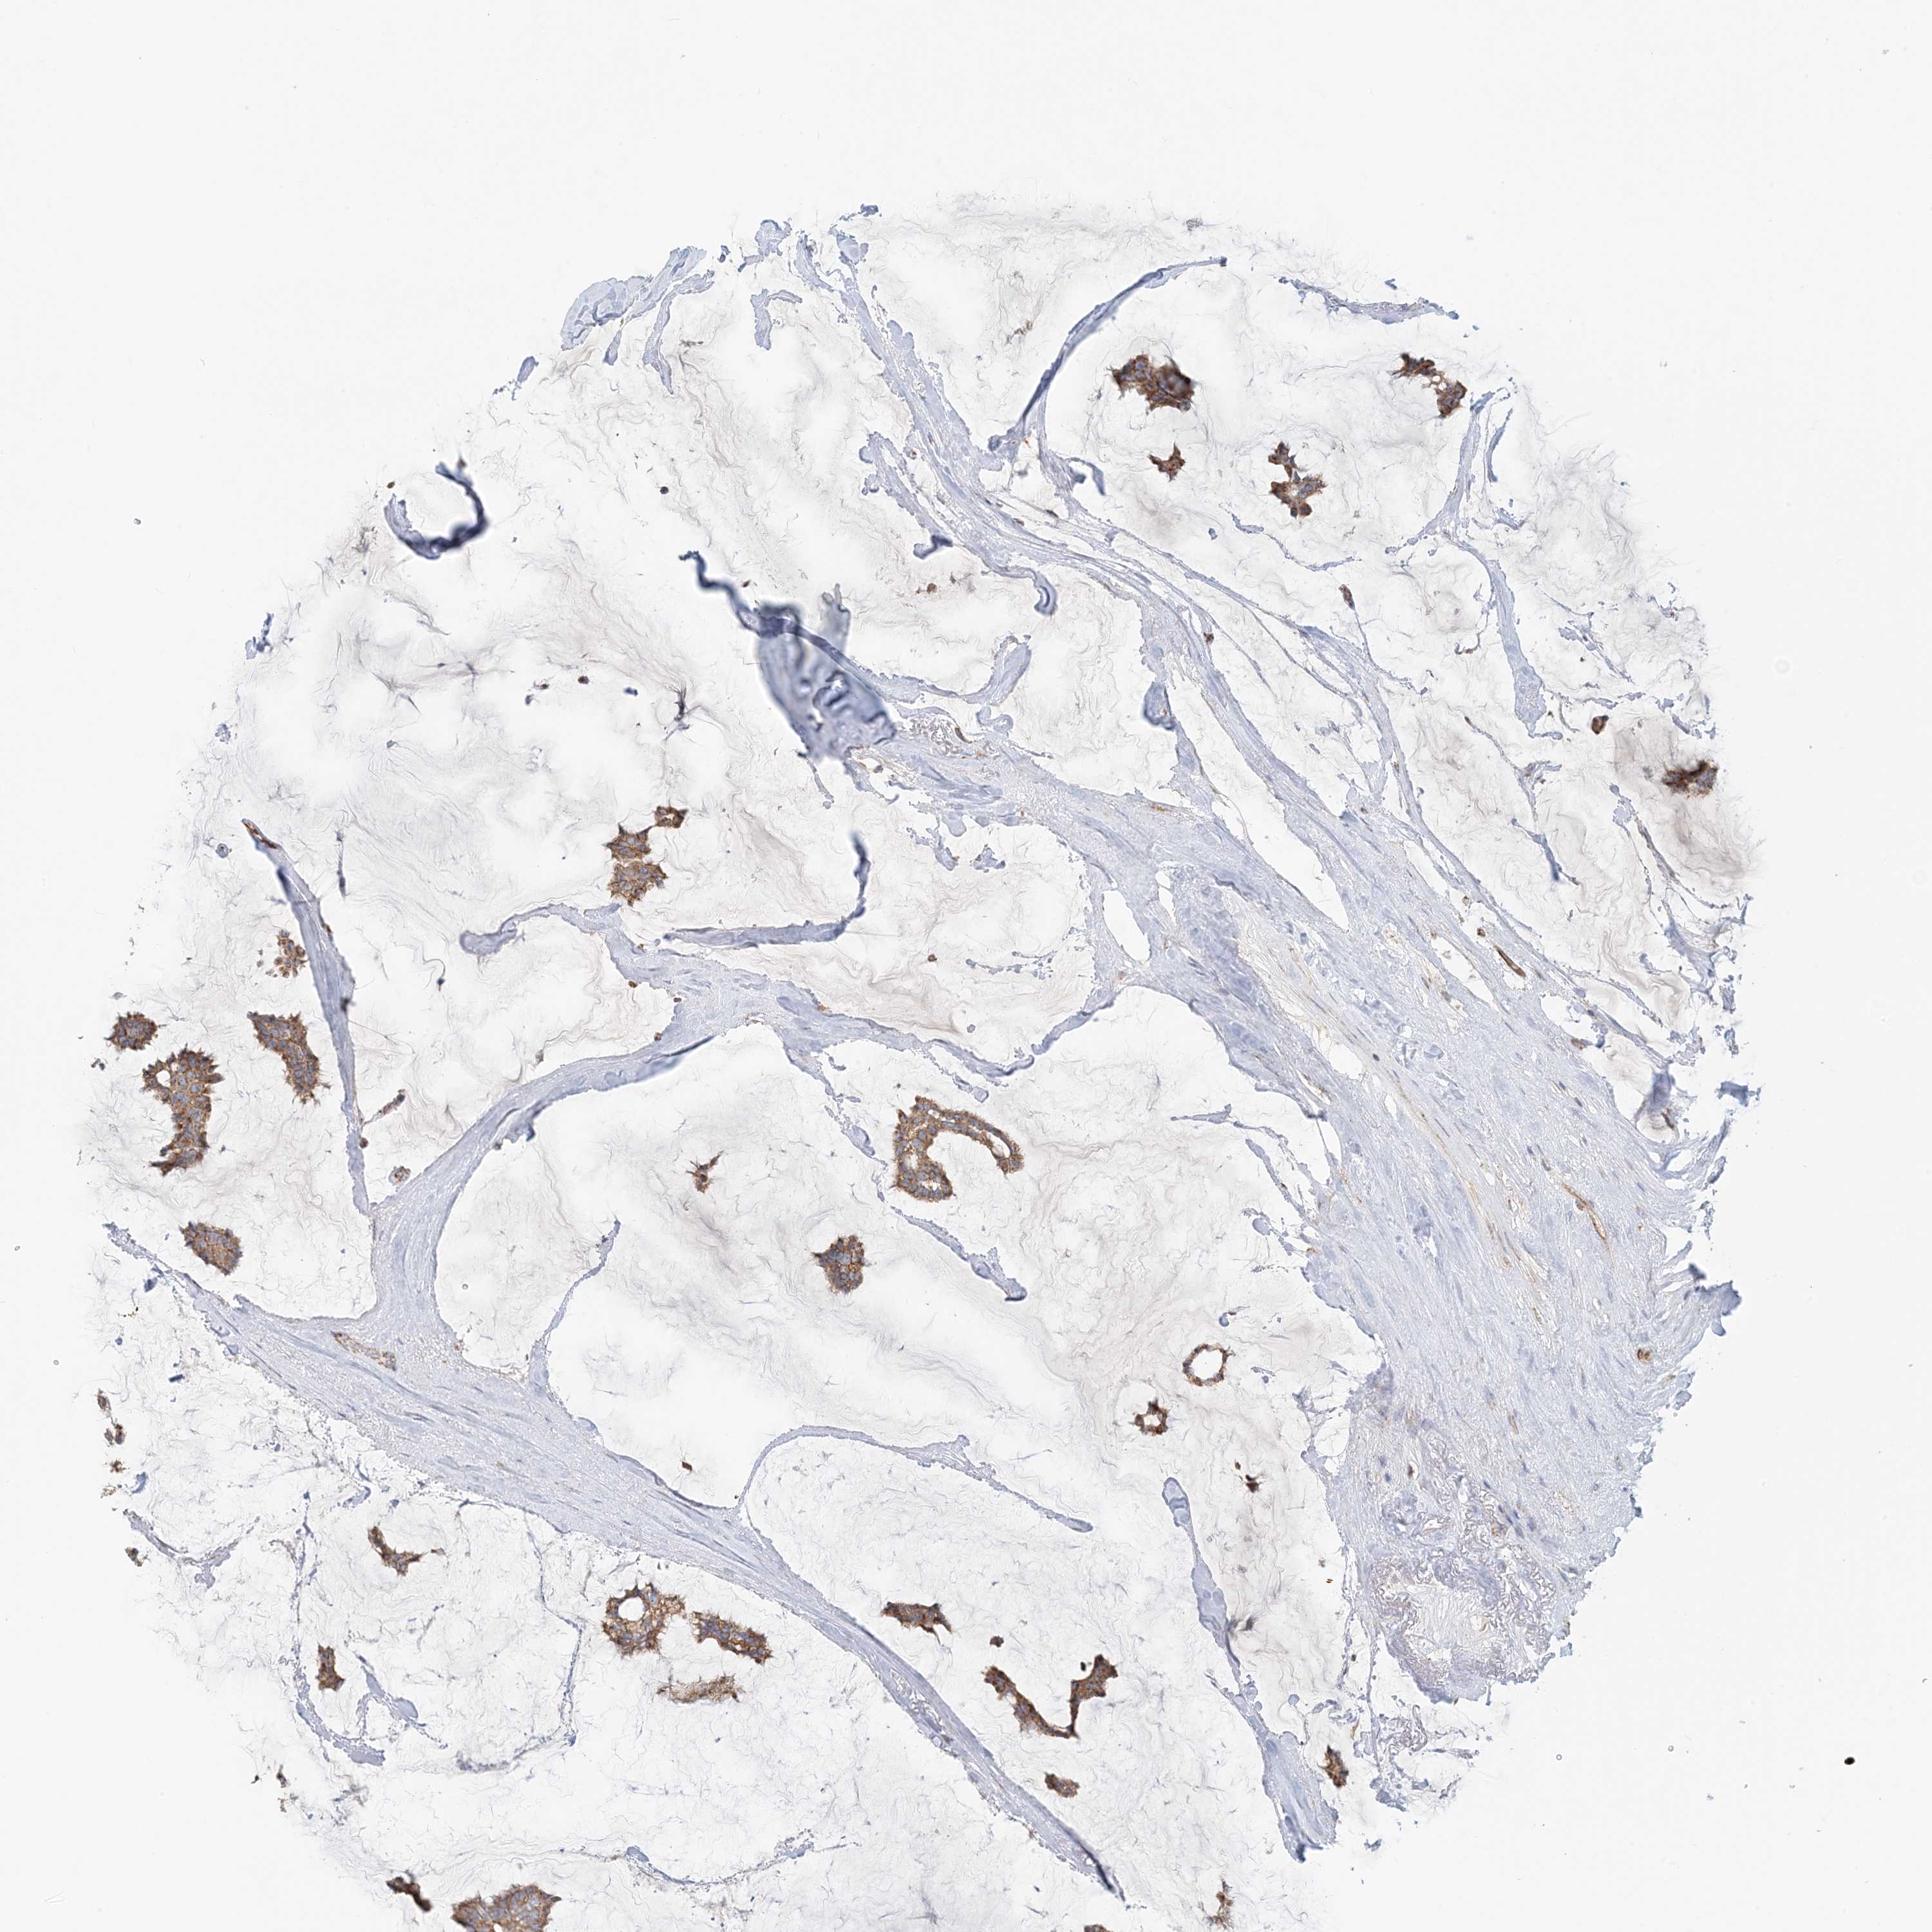

CANCER BREAST CANCER Show tissue menu

BRCA TCGA BRCA VALIDATION PROTEIN EXPRESSION

ANTIBODIES

AND

VALIDATION